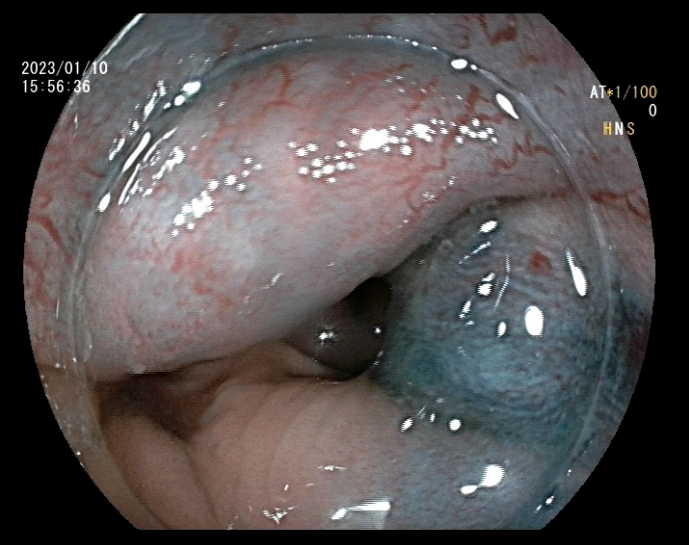

患者李某,男,48岁,主因间断便血2月余,加重20天入院。既往高血压病1级(低危)、高脂血症。患者饱受2个多月间断鲜血便的困扰,且便后伴有异物脱出,门诊以“II期内痔伴出血”收入消化内科。消化内科副主任王铁汉查房时,根据患者目前状况及手术耐受情况,建议其行内镜下内痔硬化剂注射术,并与患者讲解了此术式的优点及相关事项,经过衡量再三,患者同意实施内镜下治疗。

入院的第三天,张芙蓉主治医师在王铁汉副主任的指导下,为患者实施内镜下内痔硬化剂注射术,仅数分钟,手术成功完成。术后患者无任何不适症状,并于三日后出院,术后第7、15天随访,患者表述术后未感觉到任何不适,困扰多月的血便问题得以完美解决。

近几年,内镜下内痔硬化剂治疗术已广泛应用于各大医院,该治疗方法适用于I期、II期、III期内痔及混合痔内痔部分,尤其是内痔出血患者效果尤佳。患者接受程度高、效果满意。该治疗在做电子结肠镜过程中即可完成,较传统的痔疮治疗方法,操作简单,患者痛苦小,疗效好,并发症少,且花费低,患者耐受性好,术后观察2-3天无不适症状即可出院。